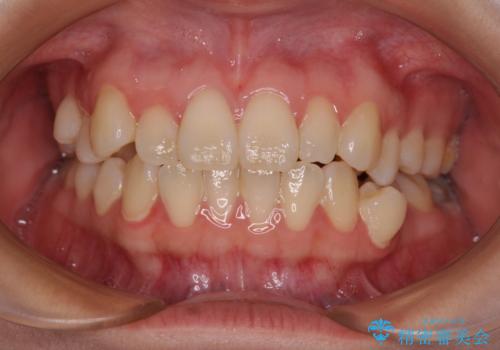

最新の症例

Latest cases